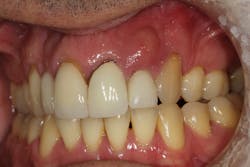

These alveolar bone changes often compromise implant placement due to thin bone volume (figures 2a–2d).

Reduction in quantity and quality of bone can also compromise functional and esthetic outcomes of both implants and fixed bridge restorations (figures 3 and 3a).